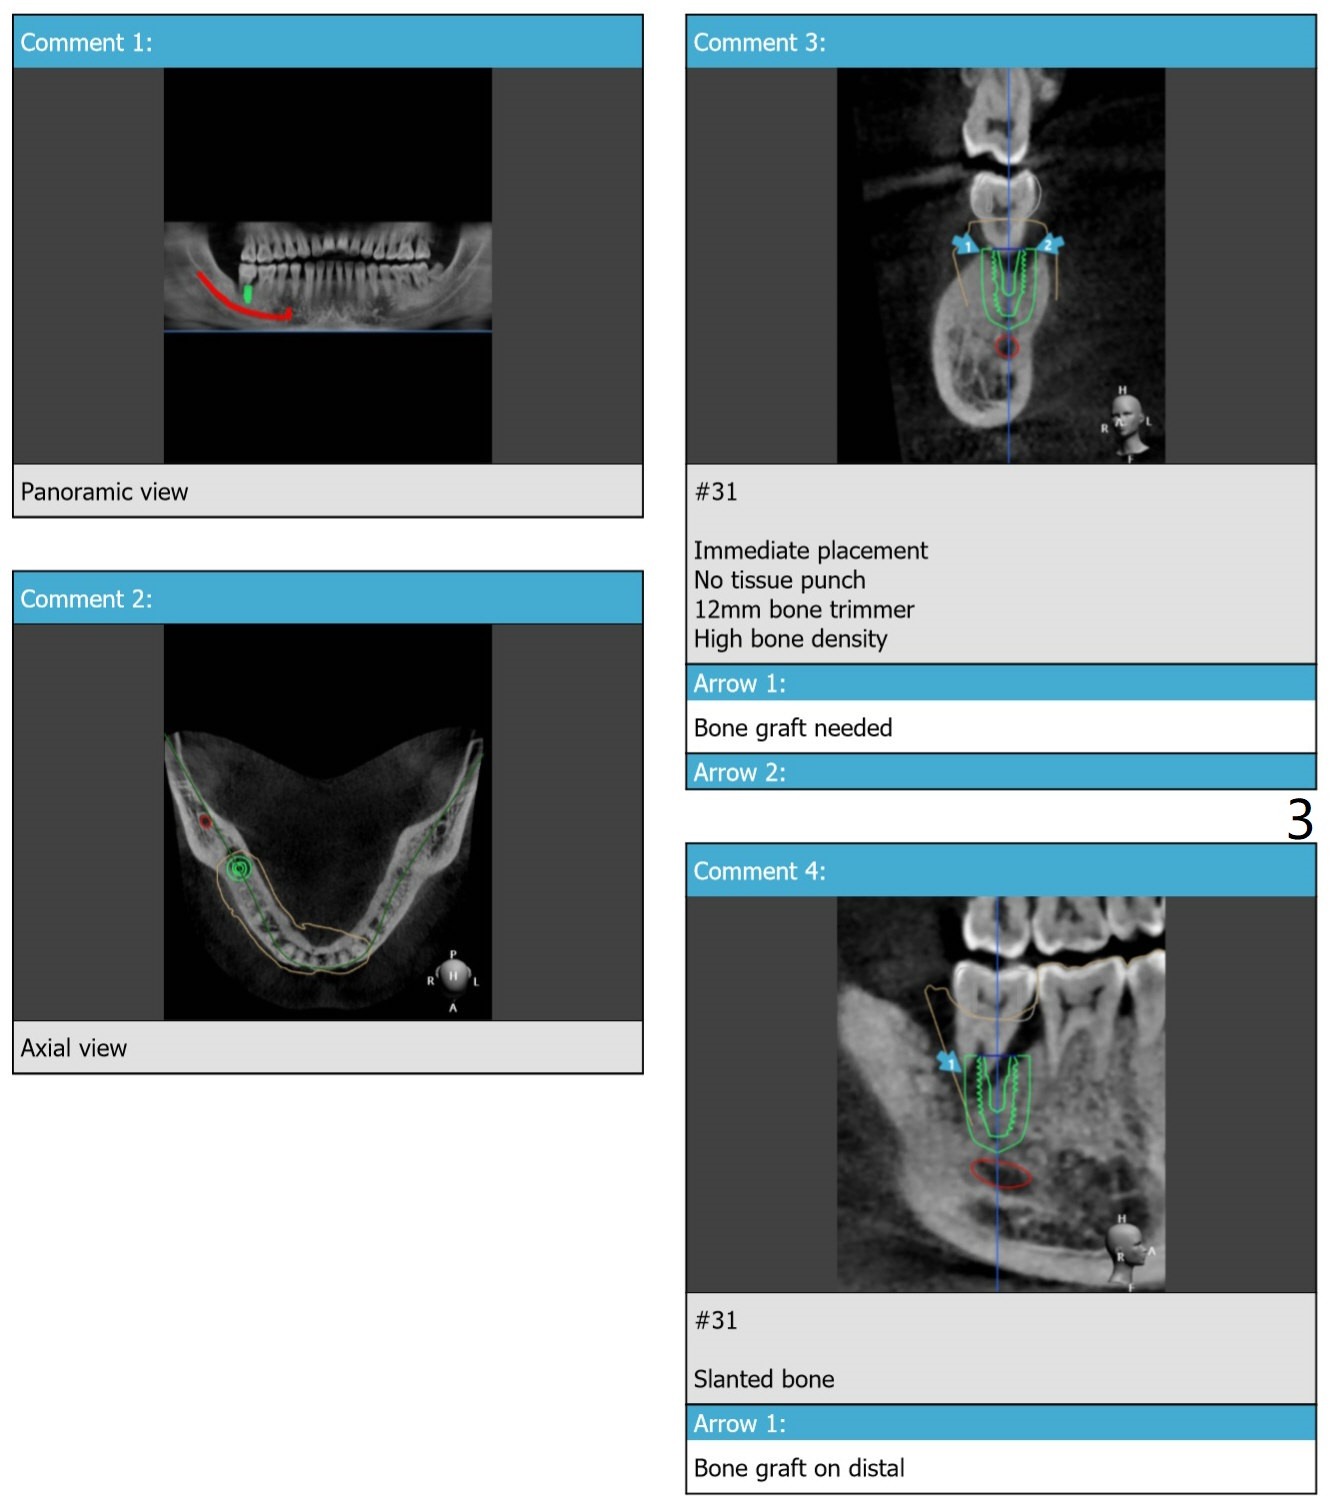

Slanted Bone M

A 40-year-old man requests extraction of the tooth #31 with severe bone loss. PRF will be prepared for sticky bone and membranes (x2).

Lower

Molar Immediate Implant,

Prevent Molar Periimplantitis (Protocols,

Table),

Trajectory II,

No Antibiotic